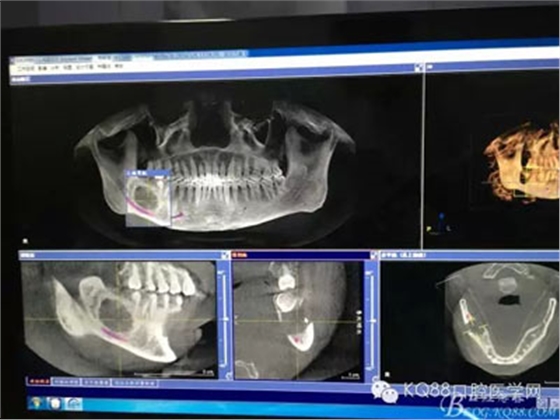

圖2.術(shù)前的CBCT檢查:48下方頜骨橢圓形囊性陰影,下方接近下頜管。

圖3.這張重建的全景片,似乎48就漂浮在囊腔上方,由此感覺48拔除如同探囊取物一般。

圖4.三維重建也提示:48拔除難度不大